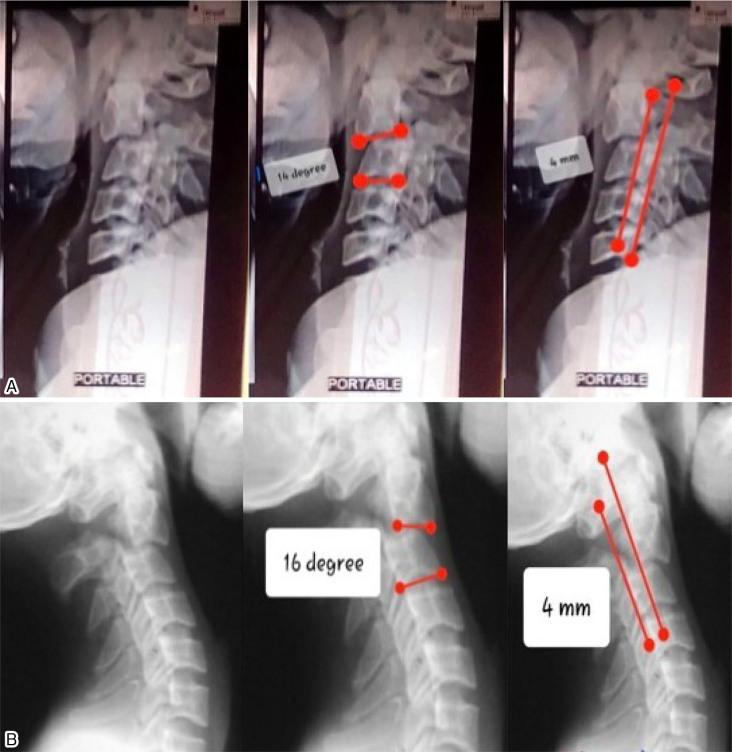

Postoperatively, C2-C3 angulation improved significantly, decreasing from 15° to 4.4°, and sagittal translation improved from 4.2 mm to 2 mm. The VAS score improved from 6.4 to 1.4 at 24 months postsurgery. Concurrently, NDI decreased from 70.4% to 14.8%. Fusion occurred in an average of 5.6 months. Neurologically, one patient improved from ASIA grade D to grade E, while the other four retained their grade E status.

A single-stage ACDF with autologous iliac crest bone grafts is an effective surgical option for neglected type II/IIA Hangman's fractures, yielding satisfactory functional and radiological outcomes. This technique significantly corrects anterior translation and angulation, even in neglected cases, with the aid of intraoperative skull traction and plate reduction.